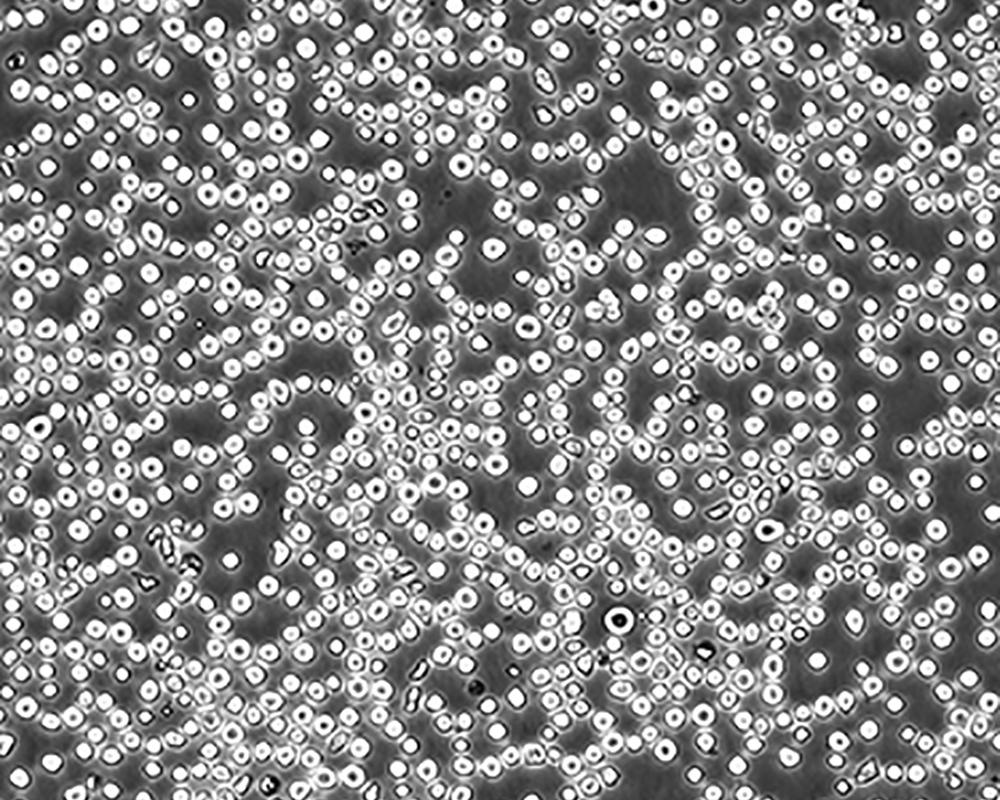

形態(tài)特征 lymphoblast

細(xì)胞描述 CEM/C1是人T細(xì)胞白血病細(xì)胞株CCRF-CEM(見ATCC CCL-119)具有喜樹堿抗性的衍生株。1991年細(xì)胞株選擇并亞克隆了對CPT的抗性。細(xì)胞表現(xiàn)出對CPT類似物水溶性的托泊替康和非水溶性的9-氨基-CPT及10,11-亞甲二氧基-CPT具有交叉抗性。CEM/C1細(xì)胞對CPT的敏感性較母系CEM細(xì)胞低31倍。CEM/C1細(xì)胞表現(xiàn)非典型的多藥抗性和轉(zhuǎn)換拓補(bǔ)異構(gòu)酶I催化活性。對CPT的抗性維持6個月以上。